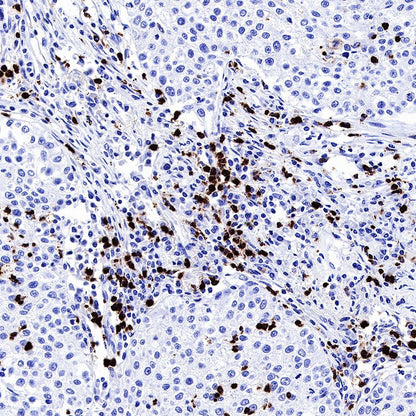

IHC shows positive staining in paraffin-embedded human lung squamous cell carcinoma. Anti-MPO antibody was used at 1/1000 dilution, followed by a HRP Polymer for Mouse & Rabbit IgG (ready to use). Counterstained with hematoxylin. Heat mediated antigen retrieval with Tris/EDTA buffer pH9.0 was performed before commencing with IHC staining protocol.